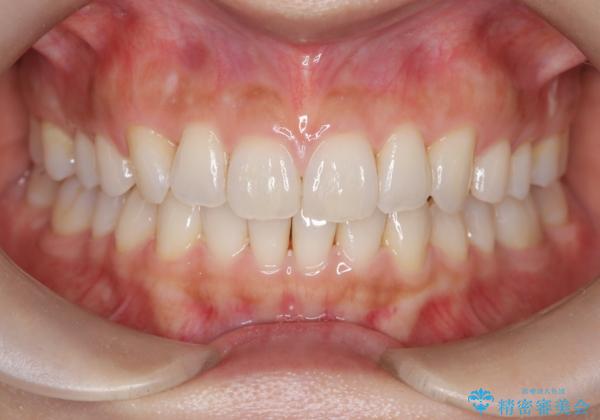

【インビザライン】前歯のねじれを治したい

- 前歯のガタガタを主訴に来院されました。

叢生の量は軽度でしたが臼歯の遠心移動を行い、インビザラインにて治療をしました。

叢生の改善に必要なスペースは遠心移動やIPRで作ることが可能です。今回は遠心移動をメインにスペースを作って叢生の改善を行いました。